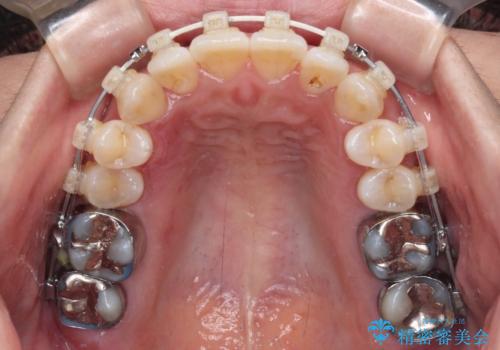

- 審美装置

- 2年6ヶ月

ワイヤー矯正でもインビザラインでも対応可能でしたが、上顎歯列が前方位であるときには、ワイヤー矯正の方がより良い仕上がりとなる可能性が高いため、ワイヤー矯正をおすすめいたしました。